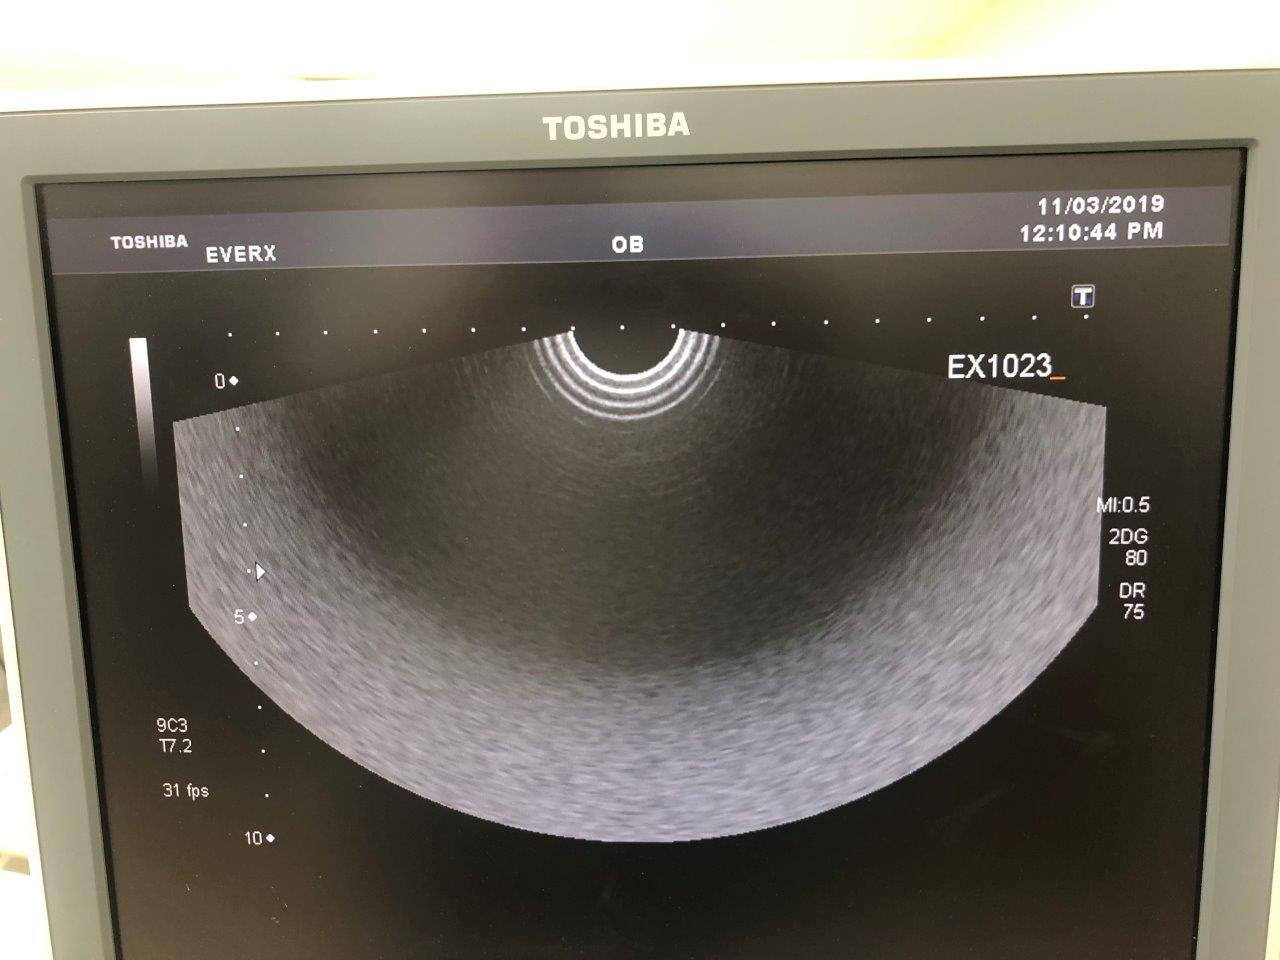

Used Toshiba Xario XG – good condition

Our Ref no. EX1020,

Multiple Probes to choose from: PVT 375BT, PVT 661VT, PLT 1204AT, PLT 704SBT